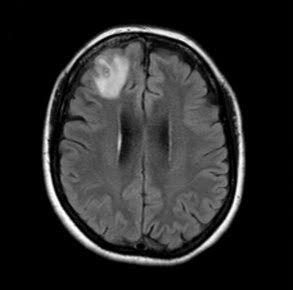

Doctors ordered an MRI scan of her brain

In 2022, she was also showing signs of depression and forgetfulness, so doctors ordered an MRI scan of her brain, which revealed abnormalities that led doctors to recommend surgery.